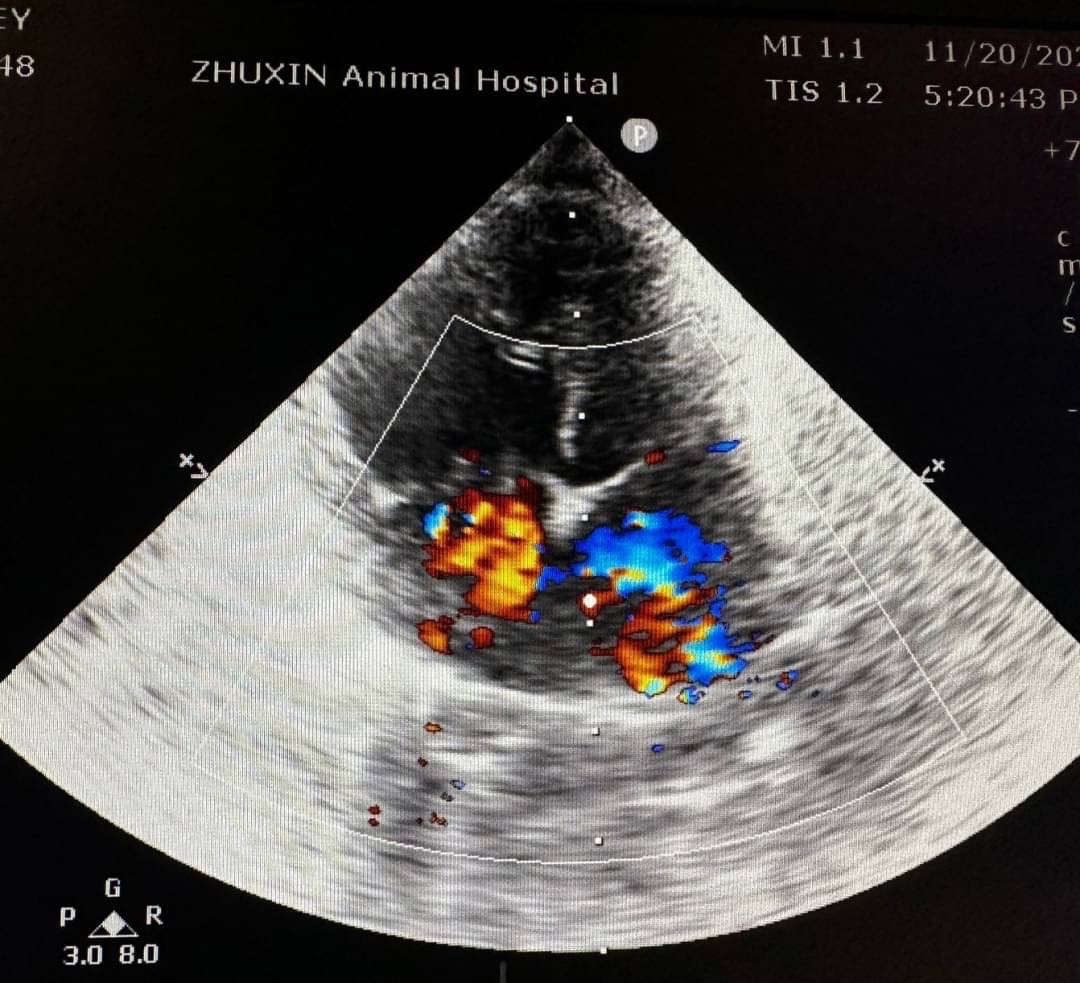

心臟科

心臟腫瘤

• 貓咪的心臟病

• 狗狗心絲蟲症外科治療 夾蟲手術狗狗心臟病

• 淺談貓心臟超音波快速掃描(QUICK SCAN) 的意義    貓咪心臟病 貓心臟超音波檢查

• 狗貓心臟病 心絲蟲感染 心臟外科手術 心絲蟲夾蟲手術

• 心臟科

• 狗狗 肺高壓